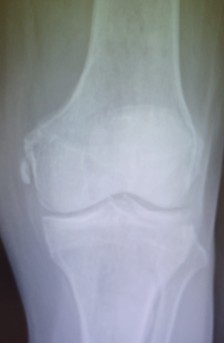

Dos ejemplos de Enfermedad de Pellegrini -Stieda.

La enfermedad de Pellegrini–Stieda se caracteriza por la osificación o calcificación postraumática del ligamento colateral medial (LCM) de la rodilla, habitualmente en su inserción femoral. En las radiografías se observa una imagen lineal o curvilínea adyacente al cóndilo femoral medial. Cuando este hallazgo se asocia a dolor, rigidez o limitación funcional, se denomina síndrome de Pellegrini–Stieda (Contreras, 2003).

- Radiografía: muestra calcificación curvilínea o lineal adyacente al cóndilo femoral medial (Panadero et al., 2012).